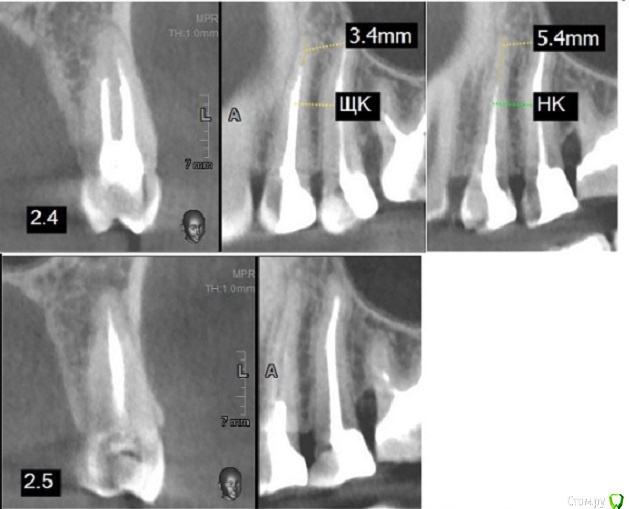

Подскажите пожалуйста, нужно ли перелечивать полностью (с перепломбировкой каналов) 4 и 5 зуб? Постоянно теперь в области 5-4 зуба  неприятное ощущение, на 5-ом есть сбоку в самом низу пятно,  думала, что кариес, но врач сказала, что это не кариес, возможно шов (одна пломба новая, другая старая) ? (может не так поняла), это было до кт.

Если ущипнуть сильно кожу в этой области, то эти неприятные ощущения (вроде боли) чувствуются в области 5-1 зубов. Ощущение, что как будто бы чешется, похожи немного на ощущение, которое бывает после пломбировки канала, установки пломбы, когда наркоз отходит. Чувствительность на горячее (аж в корни куда-то идет). Это проблема в зубах (корни не до конца запломбированы, но раньше не мешало это, да и наверное способность кт выше? поэтому и видно сейчас это?).Или невралгия все же?  Еще как будто бы зуб 5 мешает нижнему ряду.

Ниже фото 4,5 и 6 на всякий случай.